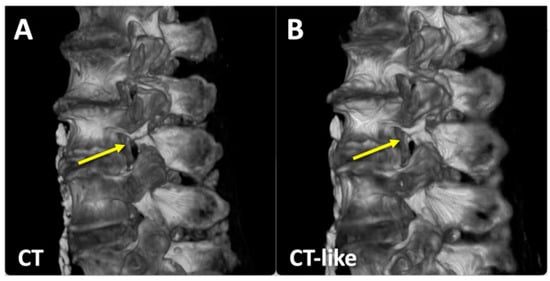

3.1. CT-like Images